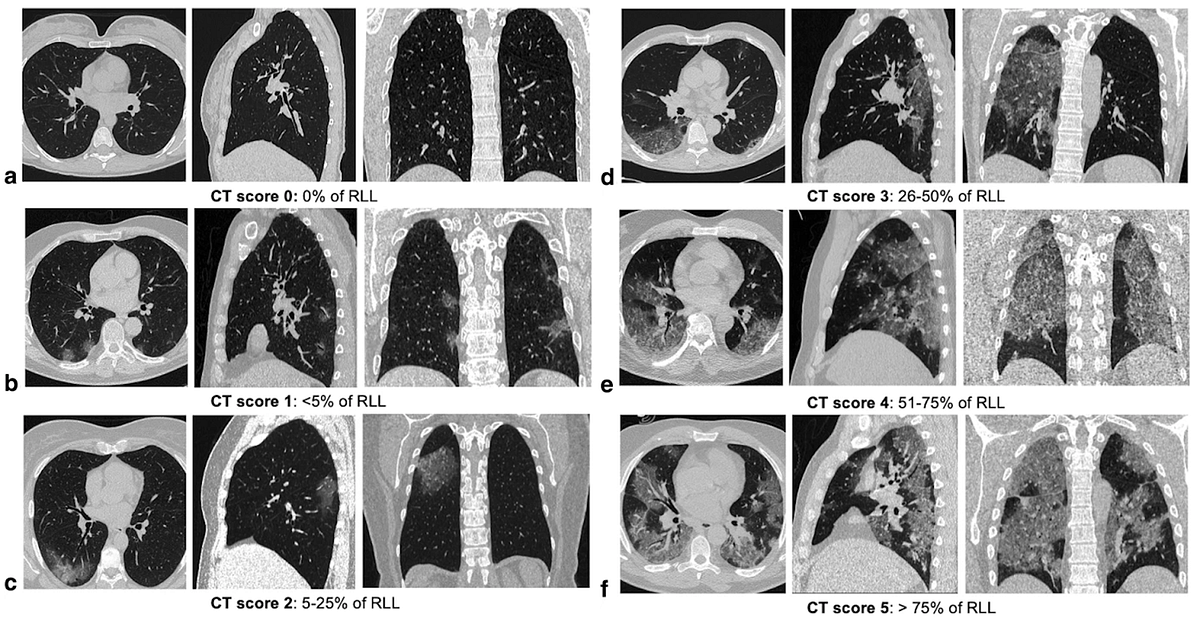

Correlation Between Chest Ct Severity Scores And The Clinical Parameters Of Adult Patients With Covid 19 Pneumonia Medrxiv